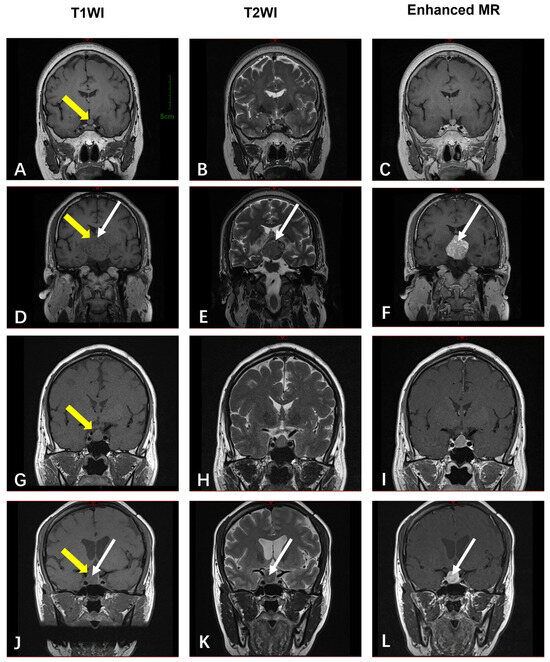

| MRI (n = 4) | T1-hypointense (n = 3, 75%) or T1-isointense (n = 1, 25%); variable T2-signals (hyper-/mixed). | N/A (all benign) | |

| Sellar Region | MRI (n = 4) | T1-isointense; T2-variable (“star-like crack signs” in 50%); heterogeneous enhancement in 50% | N/A (all benign) |